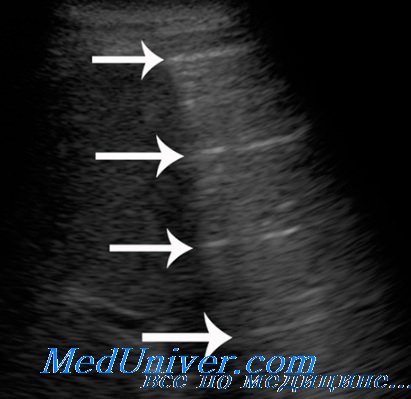

По мере нарастания воздушности внутрилегочная граница инфильтрата в прикорневой зоне становится все более неровной и нечеткой за счет увеличения числа и размеров воздушных участков. Сливаясь между собой, они приводят к уменьшению наружно-внутреннего размера зоны инфильтрации, и глубина распространения ультразвука в легкое постепенно снижается. Инфильтрат становится менее глубоким, хотя его поперечные размеры, а, следовательно, и площадь проекции на грудную стенку уменьшаются не так быстро. В результате форма инфильтрата из неправильно овальной становится близкой к треугольной, наблюдаемой при сегментарном поражении. Таким образом долевая ультразвуковая форма постепенно сменяется сегментарной.

Внутрилегочные контуры по всему периметру безвоздушного участка становятся все более неровными, ступенчатыми, местами прерываются гиперэхогенными воздушными фрагментами, клиновидно вдающимися вглубь оставшегося инфильтрата. Значительно возрастает количество реверберации и степень рассеивания ультразвука от увеличивающихся воздушных включений, что препятствует визуализации внутрилегочной границы. Инфильтрация становится все более поверхностной, медленно «тает», уступая место воздушной легочной ткани, и пневмония постепенно переходит из сегментарной формы в кортикальную.